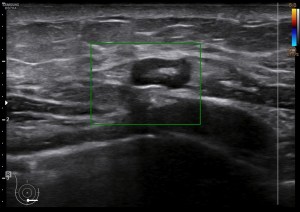

252. Mastitis.

El caso que os traigo hoy es muy sencillo, es una mastitis. Vemos muchas en la sección de mama, pueden cursar con calor local, dolor, piel de naranja y fiebre. Las mastitis habitualmente son valoradas clínicamente y diagnosticadas sin necesidad de realizar ecografía de mama, pero en ocasiones, si el tratamiento farmacológico no funciona, hay que realizar ecografía para valorar posibles complicaciones como abcesos o lesiones tumorales subyacentes.

La clínica ya la conocemos, la semiología os la presento aquí. Ecográficamente la mastitis se ve como una zona donde el tejido varía la ecogenicidad, se vuelve más hiperecogénico, aumena su tamaño, incluso su vascularización. La piel se puede ver engrosada. El tejido mamario puede verse heterogéneo, simulando lesiones de otra índole, es decir, su aspecto puede ser variado.

Ecográficamente, encontraremos una zona afectada, de la manera descrita en el párrafo superior, y junto a ella, en una zona normal, sin afectación la semiología normal de la mama.

Te presento una mastitis tipo, con un componente de resistencia al antibiótico, con lo que la paciente no mejoraba pese al tratamiento, además presentaba una colección con un tracto que abocaba en la superficie y drenaba líquido purulento a la superficie.

La imagen 1 y la imagen 2 son normalidad con anatomía básica y semilogía patológica respectivamente. Compara amabas imágenes para darte cuenta de como cambia el tejido afecto por la mastitis en este caso. No olvides que hay otras patología que pueden afectar el tejido modificando su ecoestructura normal de forma similar.

En la imagen 3 puedes ver un absceso, complicación de una mastitis, cuyo aspecto es el de una colección anecoica, que si observas, quieres buscar la superficie de la piel. La imagen 4 y 5 es el estudio de la lesión en trasnverso u otro plano y el estudio doppler buscando posible vascularización a ese nivel.

En las mastitis, al ser procesos infecciosos, no es raro ver gánglios intramamarios aumentados de tamaño o reactivos que hayan perdido su centro graso. En este caso, en localización muy próxima. Observa el aspecto habitual en forma de judia con centro hiperecogénico graso y corteza hipoecogénica, imagen 4.